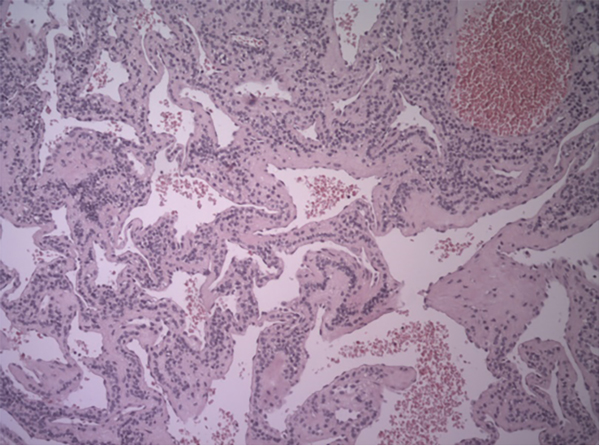

Se realizó tratamiento artroscópico de la rodilla a través de dos portales habituales AM y AL. Se constató plástica de LCA en pívot central y lesión meniscal interna, para la cual se realiza meniscectomía parcial. A continuación, se efectuó cirugía abierta, abordaje sobre masa tumoral y biopsia excisional de la pieza, de color parduzco que presenta bordes irregulares de 0.7 × 0.5 × 0.2 (figs. 3 y 4). El informe de anatomía patológica informa glomangioma como diagnóstico de la pieza enviada (figs. 5 y 6).

Figura 5: Glomangioma. Microfotografía teñida con H-E. 10X. Se observan vasos dilatados rodeados por capas de células glómicas.